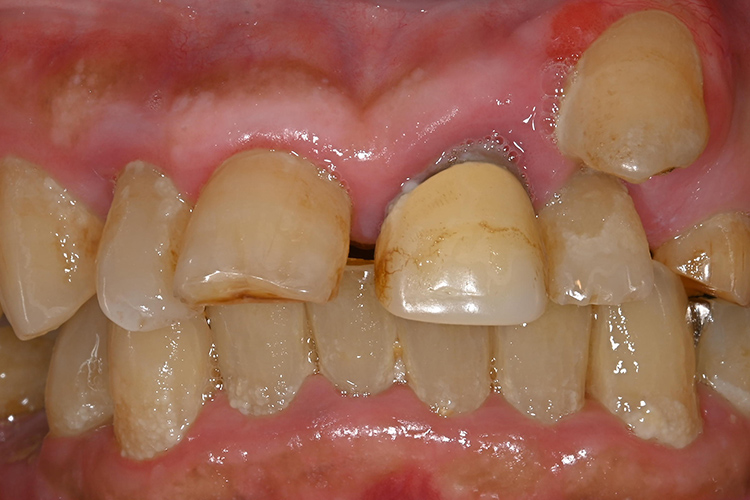

実際の実施例1

この患者様は、口腔内全体において重度の歯周病が生じており、歯磨き指導、クリーニング、Flap手術等を行ったが、歯周ポケットが深すぎるため、ブルーラジカル適用症例と診断し、施術を行いました。

(実施前)

施術前のレントゲンと口腔内写真です。施術前にプラークの除去を行ってから、施術します。